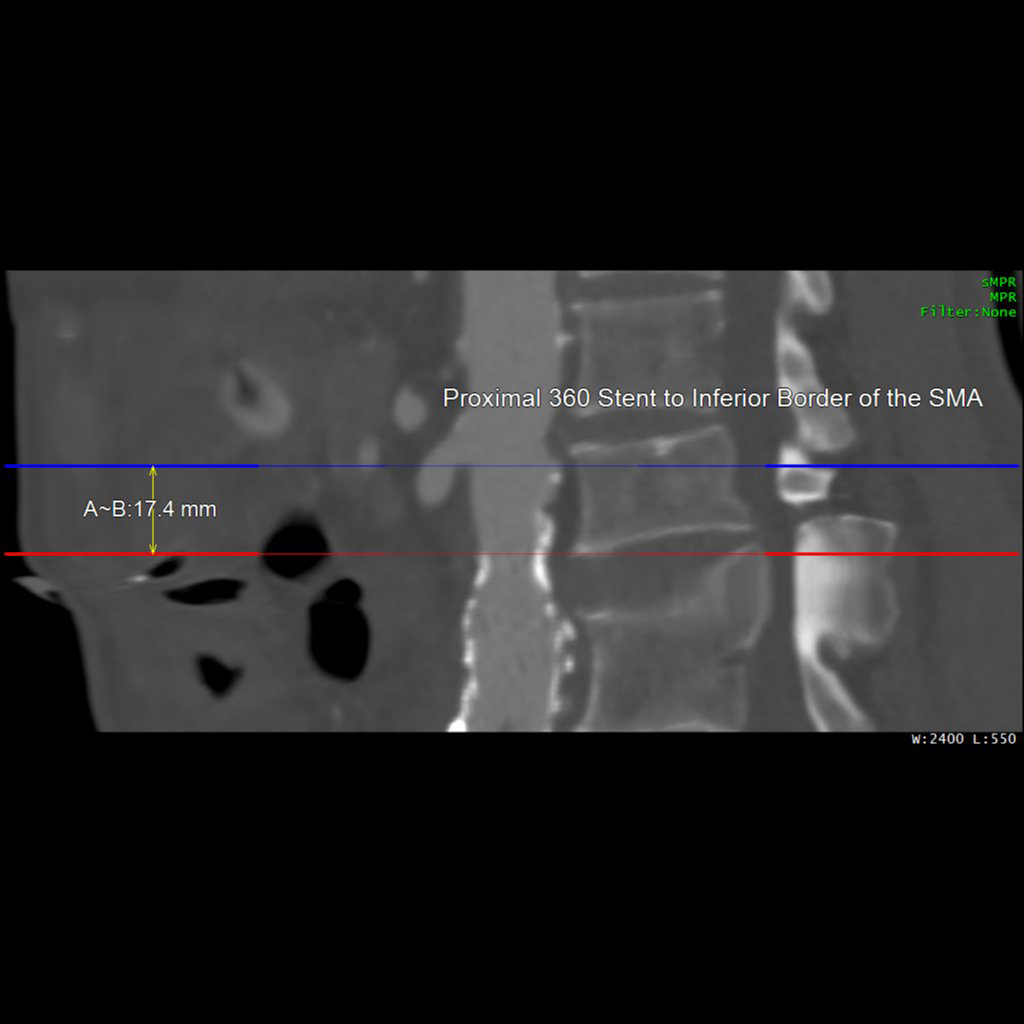

Our Post-Stent Service provides imaging for patients with stent placements in the abdominal aorta and common iliac arteries. The primary goal is to monitor changes in the maximum diameter of these vessels, ensuring early detection and management of post-stent issues. Using 3D imaging techniques identify critical aspects such as stent length, potential migration, and aortic diameter.

This protocol complements Routine Chest, Abdomen, and Pelvis imaging, offering an added layer of post-procedural monitoring. It allows quick viewing of major anatomy and focuses on identifying stent movement or aneurysm growth, ensuring comprehensive and effective monitoring.